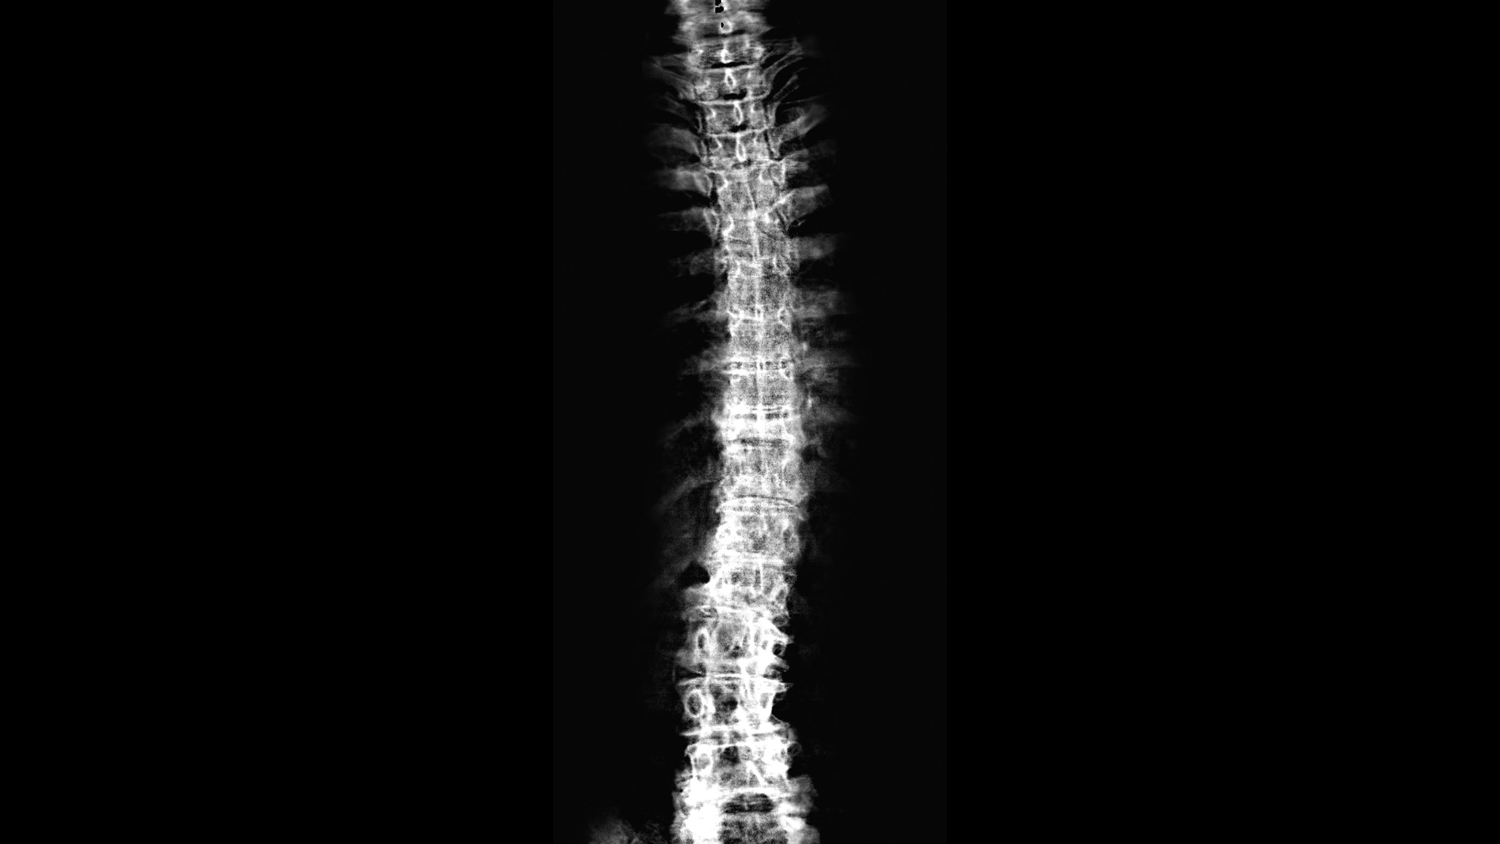

La semaine de la colonne vertébrale est un événement mondial né il y a 15 ans. Au niveau local, il est organisé pour la troisième année consécutive. "À cette occasion, nous proposons des rendez-vous d'évaluation posturale", indique Teiva Livine chiropraticien et président de l'association polynésienne de chiropractie. "Nous vérifions que la colonne vertébrale est bien alignée et nous donnons des conseils."

Le non alignement de la colonne vertébrale peut être à l'origine de douleurs au dos, mais aussi de migraines ou bien encore de troubles du système digestif, "en effet le nerf qui alimente le système digestif passe par la colonne", précise Teiva Livine. Le chiropracticien travaille sur la colonne et son placement mais aussi sur les muscles et les articulations. "Nous faisons aussi de la prévention", ajoute-t-il.

Reconnue par le ministère de la santé en France et par l'Organisation mondiale de la santé (OMS), la pratique se définit ainsi : "Médecine manuelle de référence pour les soins du dos et des articulations, la chiropraxie a pour objet la détection, le traitement et la prévention des dysfonctionnements du squelette et de ses conséquences, notamment au niveau de la colonne vertébrale et des membres.Ces dysfonctionnements se traduisent notamment par des douleurs ou une limitation du mouvement. La chiropraxie se fonde sur une conception globale du fonctionnement de l’organisme et des relations existant entre la colonne vertébrale, le système nerveux et certains troubles de la santé. Elle prend ainsi en compte les facultés de récupération du corps humain. Elle repose principalement sur les actes de manipulation vertébrale, de manœuvre d’ajustement vertébral et de mobilisation des articulations."